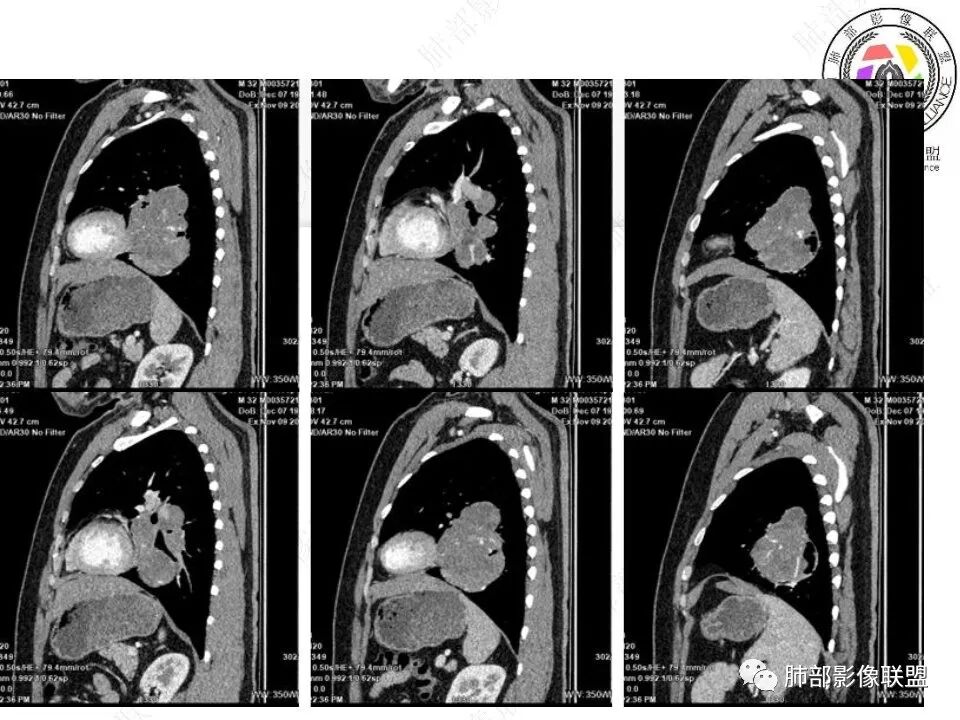

我将内部结构再重建一下

骑跨在斜裂上

局部斜裂稍增厚

下叶基底干支气管受压下移

下叶背段支气管受压稍后内移位,通畅

就是支气管目前基本没有堵塞,只是受压

下肺静脉:

还是肺动脉供血,肺静脉引流

空气新月征:

新月征很有特点,血管有特点

青年男性,体检发现左肺不规则类圆形占位性病变,叶间裂区域,定位胸膜来源。左肺下叶支气管受压狭窄,但管壁光整,未见腔内阻塞或管壁受侵。包块边界清晰,浅分叶,内部密度不均匀,病灶后份见空气新月征。渐进性强化,增强动脉期见分支状血管,蛇纹血管征。肺门纵膈未见增大淋巴结,符合孤立性纤维瘤(SFT)。